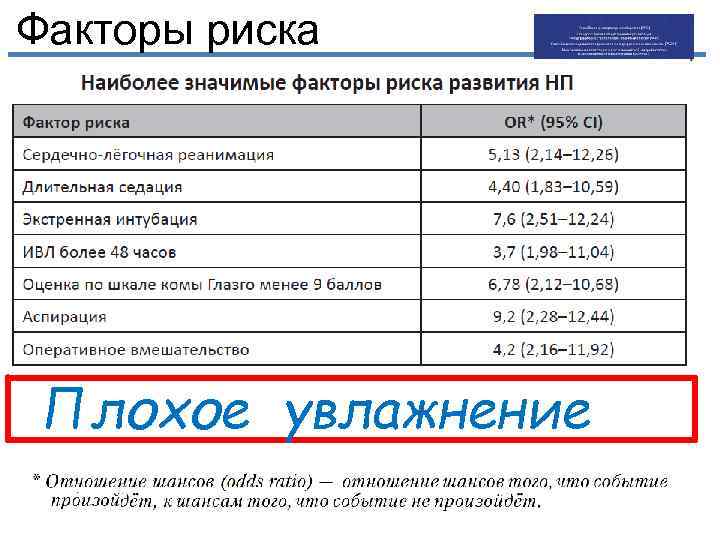

Факторы риска

Факторы риска

Факторы риска

Факторы риска

Факторы риска

Факторы риска

Факторы риска Плохое увлажнение

Факторы риска Плохое увлажнение